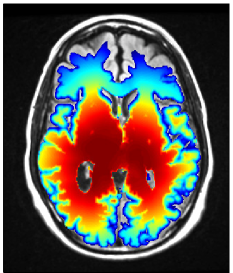

Refer to caption

Figure 3: Simulated tumor cell density based on the segmentation in figure 2 for parameters λw=4.2subscript𝜆𝑤4.2\lambda_{w}=4.2 mm and Dw/Dg=100subscript𝐷𝑤subscript𝐷𝑔100D_{w}/D_{g}=100 (a) and Dw/Dg=10subscript𝐷𝑤subscript𝐷𝑔10D_{w}/D_{g}=10 (b) . The color scale refers to the log10𝑙𝑜subscript𝑔10log_{10} cell density normalized to the carrying capacity.

In this paper, we are concerned with the spatial definition of the target volume as an isoline of the tumor cell density. In that context, the exact value of the infiltration length λwsubscript𝜆𝑤\lambda_{w} is irrelevant because it does not affect the shape of the isolines. Only the abolute values of the tumor cell density associated with the isolines are determined by λwsubscript𝜆𝑤\lambda_{w} 333The value of λwsubscript𝜆𝑤\lambda_{w} will be crucial for dose prescription considered in the accompanying paper [16].. Thus, the only relevant model parameter for this paper is the ratio Dw/Dgsubscript𝐷𝑤subscript𝐷𝑔D_{w}/D_{g}, which determines the shape of the isolines of the cell density together with the brain segmentation. The literature consistently suggests that tumor cells infiltrate gray matter much less than white matter444This holds for the most common case of astrocytomas, not necessarily for oligodentrogliomas (see [12] for a review of glioma growth patterns). This suggests a large value for Dw/Dg1much-greater-thansubscript𝐷𝑤subscript𝐷𝑔1D_{w}/D_{g}\gg 1. Most illustrations in this paper were obtained for Dw/Dg=100subscript𝐷𝑤subscript𝐷𝑔100D_{w}/D_{g}=100. The most appropriate value is however uncertain and we discuss the impact of uncertainties in Dw/Dgsubscript𝐷𝑤subscript𝐷𝑔D_{w}/D_{g} in section 3.5.

In addition to the segmentation, the ratio of white and gray matter diffusion coefficient Dw/Dgsubscript𝐷𝑤subscript𝐷𝑔D_{w}/D_{g} influences the shape of the isolines of the tumor cell density. For Dg=0subscript𝐷𝑔0D_{g}=0, gray matter represents a hard boundary and tumor cells only spread in white matter. For Dw/Dg=1subscript𝐷𝑤subscript𝐷𝑔1D_{w}/D_{g}=1, tumor cells spread equally in white and gray matter and the shape of the target is solely influenced by anatomical constraints. In figure 3 the simulated tumor cell density is compared for Dw/Dg=10subscript𝐷𝑤subscript𝐷𝑔10D_{w}/D_{g}=10 and Dw/Dg=100subscript𝐷𝑤subscript𝐷𝑔100D_{w}/D_{g}=100. For smaller Dw/Dgsubscript𝐷𝑤subscript𝐷𝑔D_{w}/D_{g}, the cell density is more washed out (figure 3b) compared to a larger Dw/Dgsubscript𝐷𝑤subscript𝐷𝑔D_{w}/D_{g} where the tumor cell density follows more closely the white matter structure (figure 3a). It has been discussed above that the cortical gray matter has a thickness of only a few millimeters. As a consequence, varying Dw/Dgsubscript𝐷𝑤subscript𝐷𝑔D_{w}/D_{g} has little impact on the global shape of the target volume. The most significant changes for this patient are around the lateral sulcus.